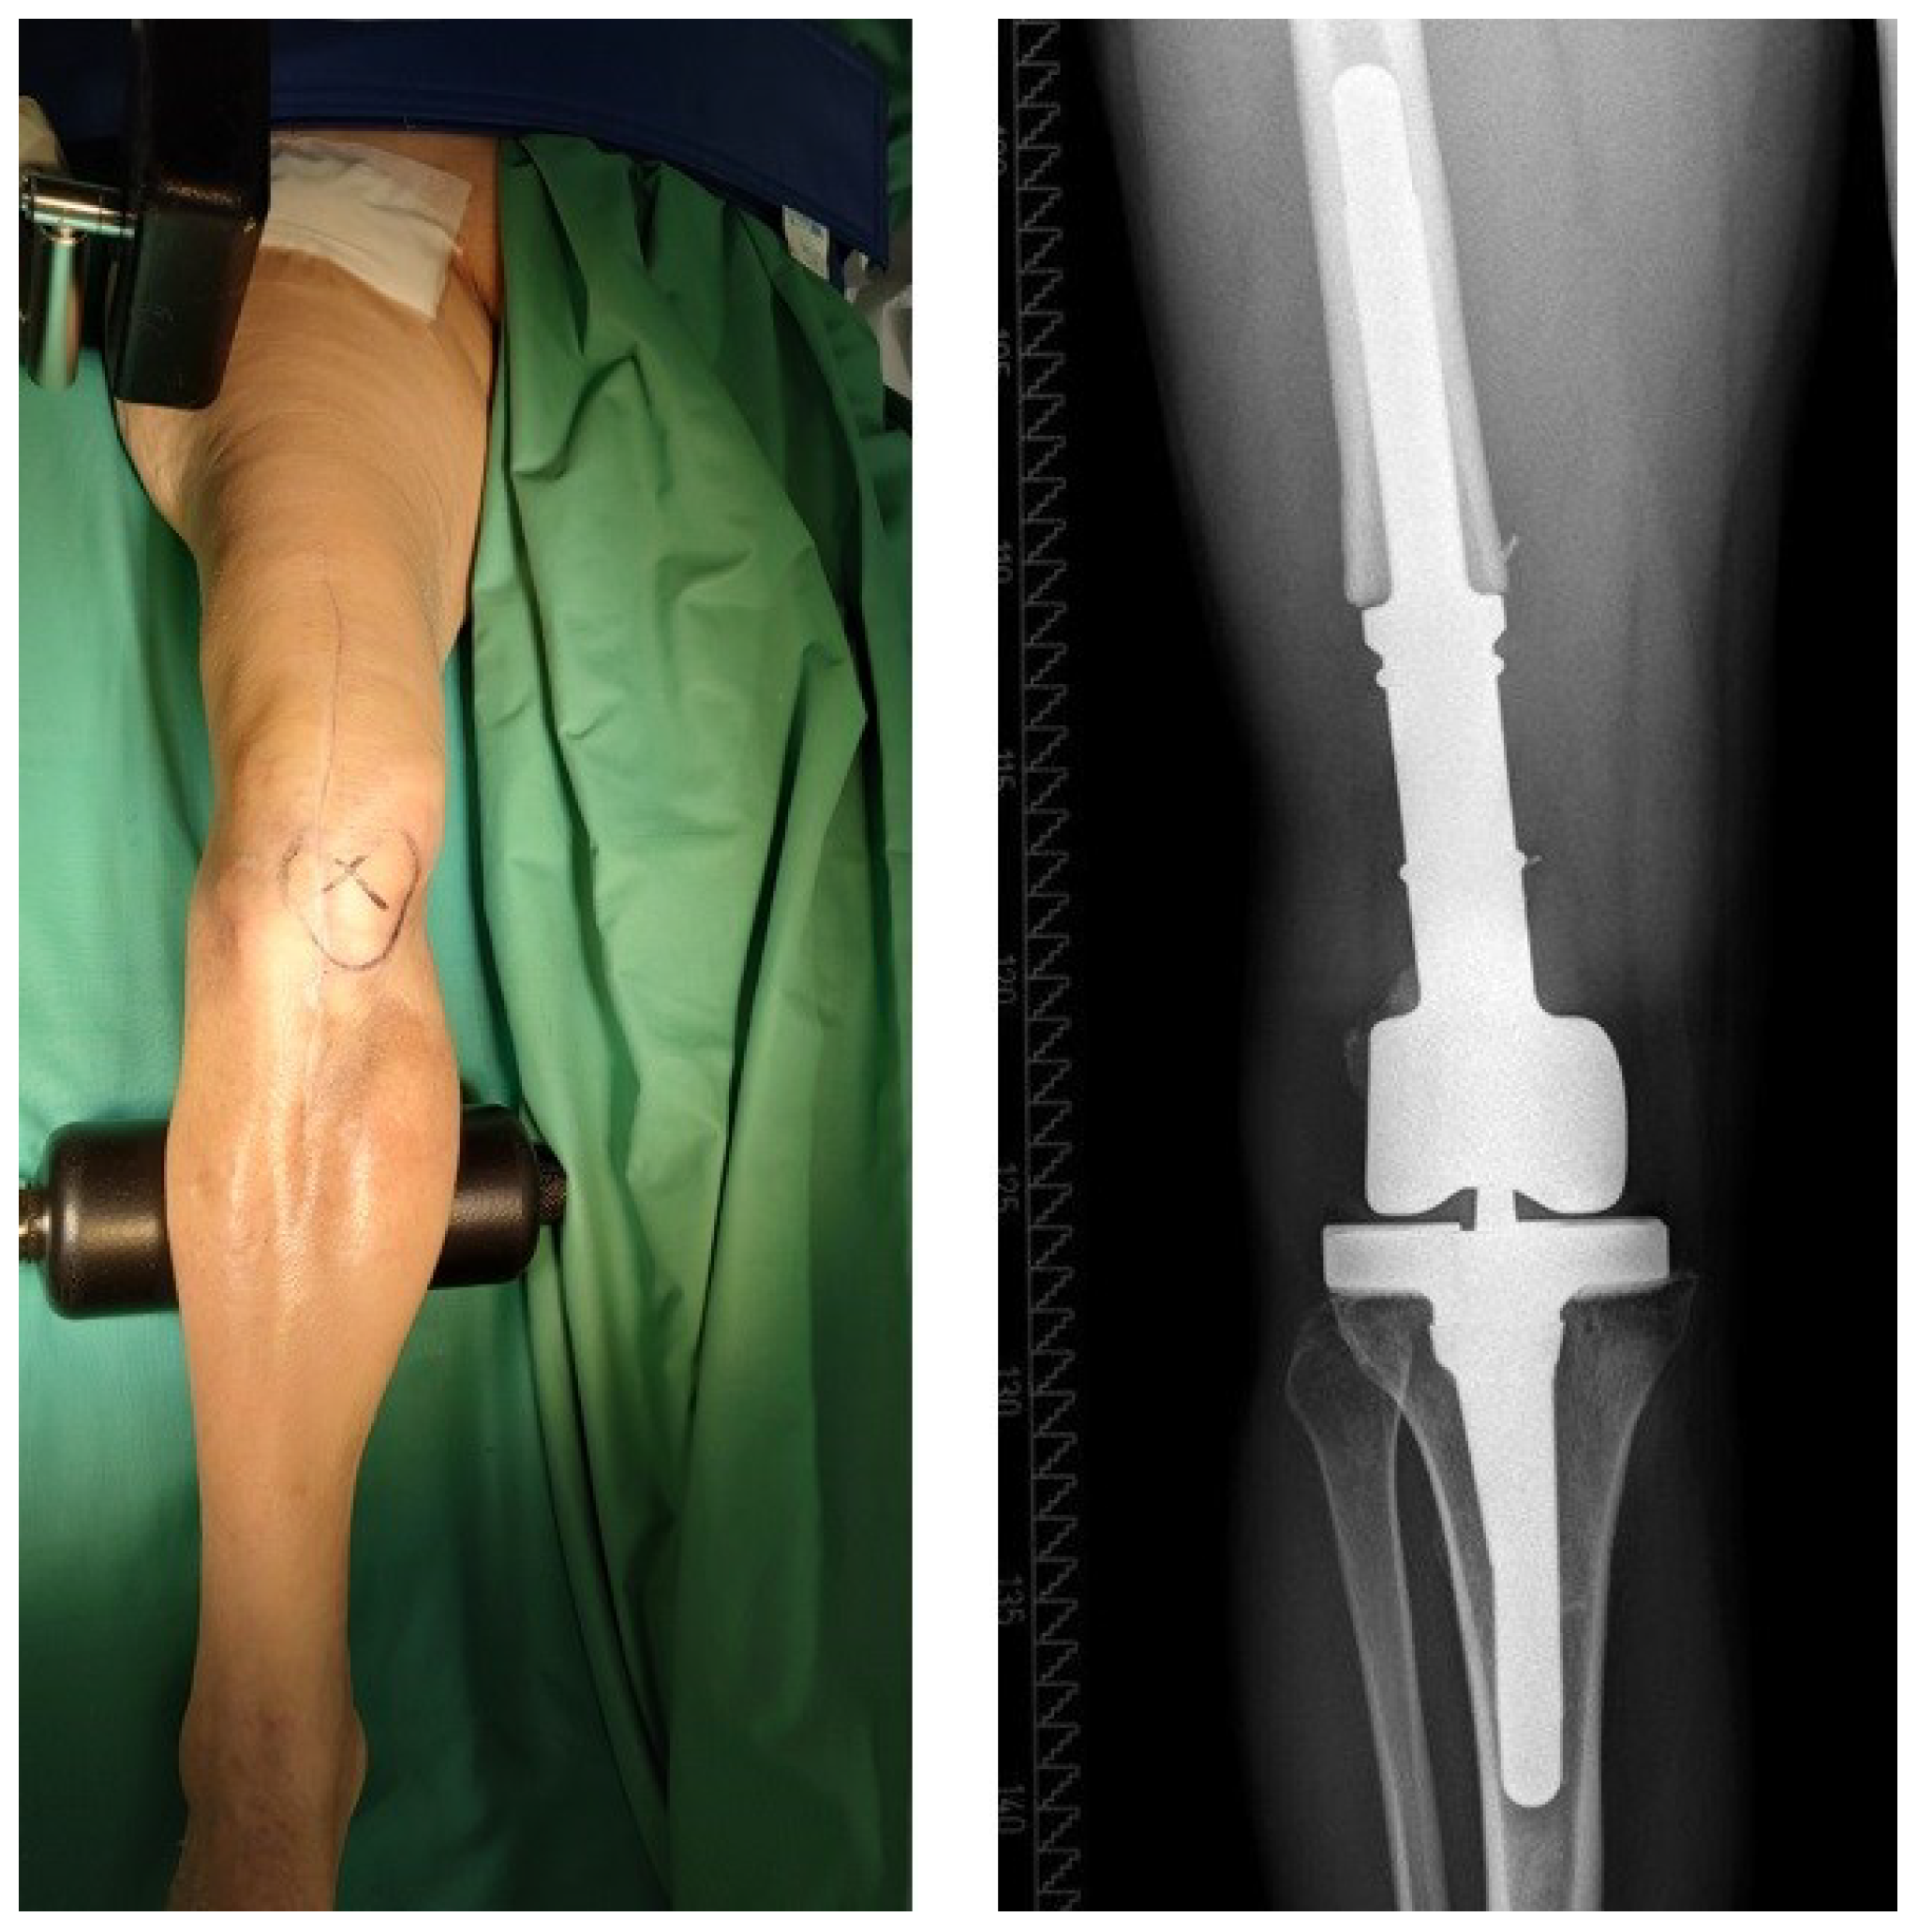

| T | T0 | a | Stable standard implant without important soft tissue defect |

| b | Stable revision implant without important soft tissue defect | ||

| T1 | a | Loosened standard implant without important soft tissue defect | |

| b | Loosened revision implant without important soft tissue defect | ||

| T2 | a | Severe soft tissue defect with standard implant | |

| b | Severe soft tissue defect with revision implant | ||